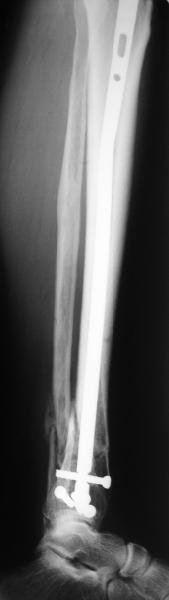

A typical case is attached, also an image with intra-op reduction obtained by a small wire distractor, in the moment of insertion a Poller wire in AP direction. Fixation by a SIGN nail. Despite the fibula was not fixed healing was obtained with the unchanged alignment.

Отправитель: Alexander Chelnokov 21 Май 2006, 23:21

I am just trying to illustrate that prevention of 1)tibial valgus and 2)loss of reduction can be provided without fibular plating. Small changes of conventional nailing techniques allow to maintain reduction of the tibia reliably without adjunctive fibular stabilization.

In delayed cases acute length restoration performed only in the tibia may leave the fibula shortened thus change the mortise. So it is reasonable to restore length of both bones simultaneously by distractor and fix the fibula not with open reduction and plating but just by a single perQ screw. Example attached.